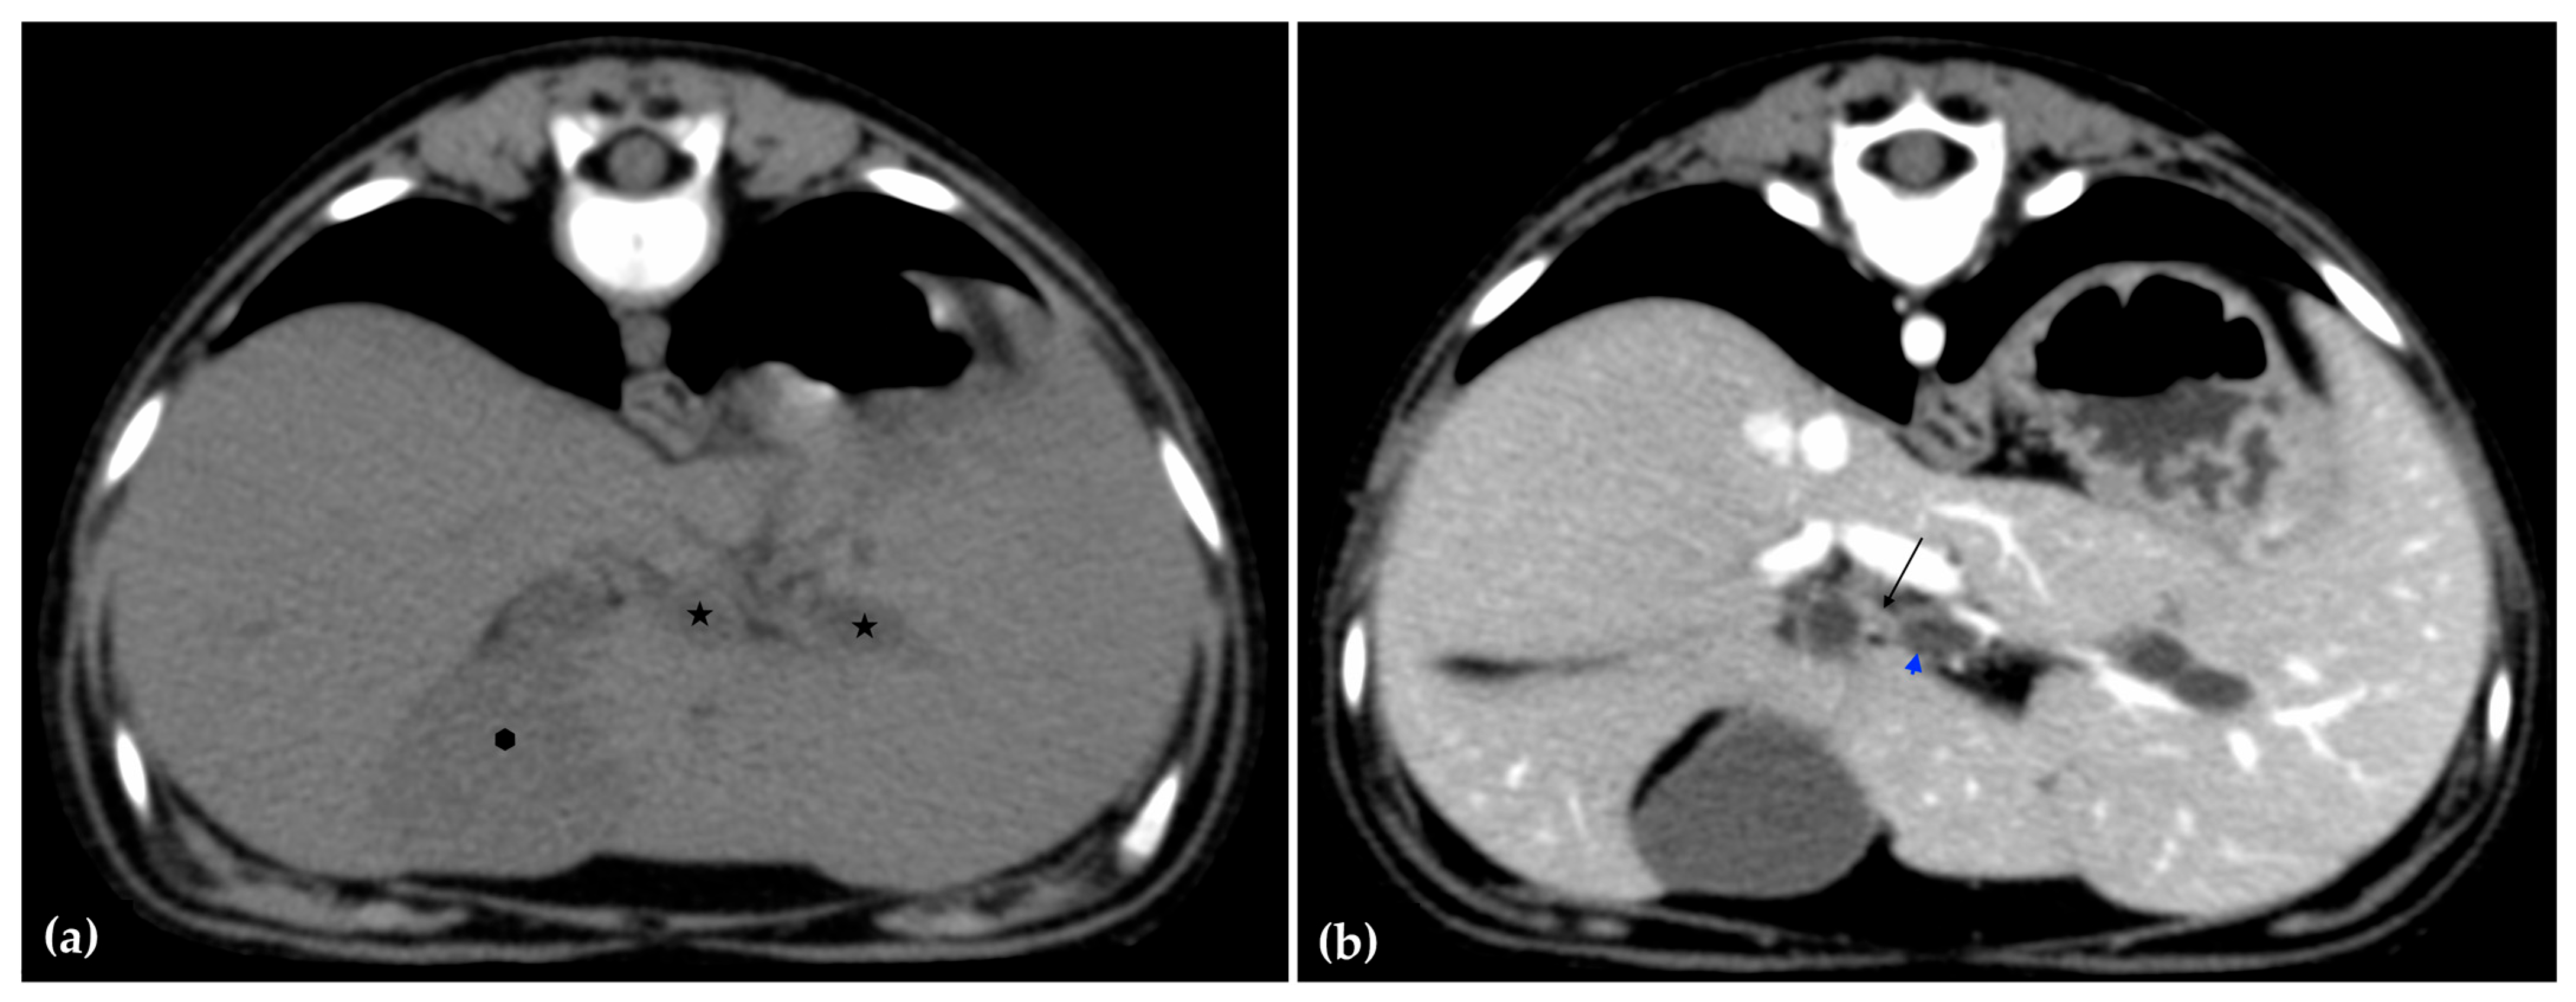

The patient was positioned in sternal recumbency. Helical scans of the abdomen using a multidetector CT were obtained with pre-contrast, post-contrast arterial, portal, and delayed images, all in a soft tissue reconstruction kernel (acquisition parameters: Slice thickness 0.9 mm, pitch 0.8, tube rotation time 0.5 s, 412 mA, 120 kVp, 512 × 512 matrix; Philips Brilliance-40, Philips International B.V., Amsterdam, Netherlands). Prior to contrast administration, the gallbladder was noted to be filled with predominantly mildly hyperattenuating (av. 25 HU) fluid. Dilation of the distal left intrahepatic biliary ducts were again seen (Figure 3a). Following intravenous contrast administration (Optiray 350™ Ioversol, Mallinckrodt Inc., Hazelwood, MO, USA; or Omnipaque 350™ Iohexol, GE Healthcare Inc., Marlborough, MA, USA), multifocal dilation and tortuous narrowing of the CBD was seen and best appreciated in the portal phase. There was increased conspicuity of the walls, both in contrast enhancement and wall thickness (Figure 3b and Figure 4a,b). No intraluminal debris or extraluminal structures to explain the multifocal dilation was appreciated.

Figure 3.

Computed tomographic (CT) pre-contrast image of the liver at the level of the gallbladder (hexagon). There is distention of the left distal intrahepatic biliary ducts (stars). The right of the patient is on the left (a). Computed tomographic (CT) post-contrast image (portal phase) at the level of the cystic duct (black arrow). Immediate dilation of the common bile duct (blue arrowhead) (b).

Overall, abdominal ultrasound and subsequent CT imaging confirmed multifocal narrowing of the biliary outflow tract. Two regions of marked stenosis were identified: one at the junction of the common bile duct with the cystic duct, and a second at the major duodenal papilla. These findings were consistent with biliary outflow obstruction. There was no evidence of portosystemic shunting or other vascular anomalies.